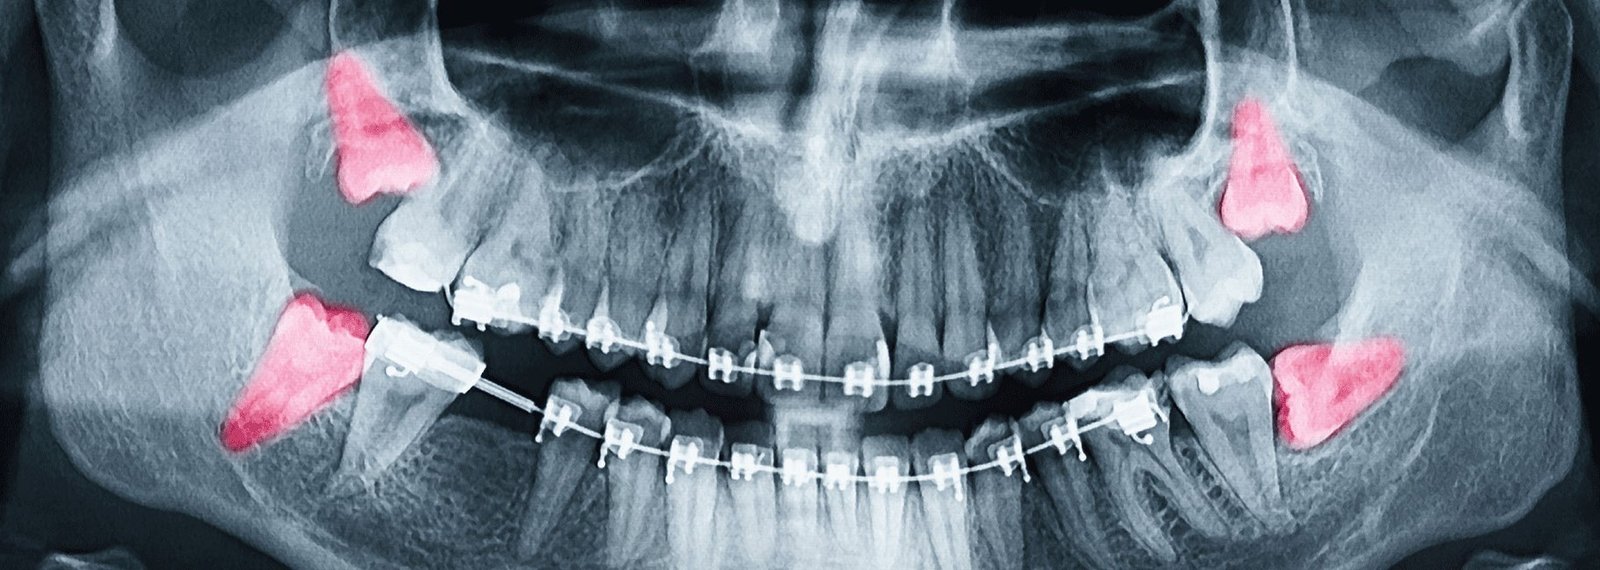

At Manchester Dental Practice, when we remove an impacted wisdom tooth, our highly trained dentists will take an X-ray to assess the tooth’s position in the gum first of all.

For most people, they are the last teeth to emerge usually in the mid-twenties. By the time your wisdom teeth come through, there may not be enough space in your mouth for them to grow well. This causes an “impacted” wisdom tooth- where it gets partially stuck in your gums, or grows at an angle.